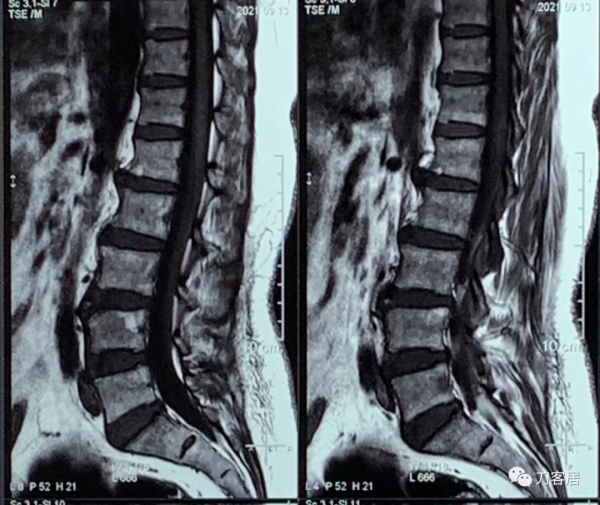

自帶腰椎MRI未見嚴重的椎間盤突出及椎管狹窄。自帶髖關節MRI未見異常,自帶胸椎MRI未見異常。自帶頸椎MRI提示頸4-5,頸5-6椎間盤突出,頸椎失穩。

圖6. 20211004胸椎MRI矢狀面T2相,未見明確的胸椎管狹窄。

圖7. 20211004胸椎MRI矢狀面T1相,未見明確的胸椎管狹窄。

圖8. 20211004胸椎MRI矢狀面及橫截面,未見明確的椎管狹窄。